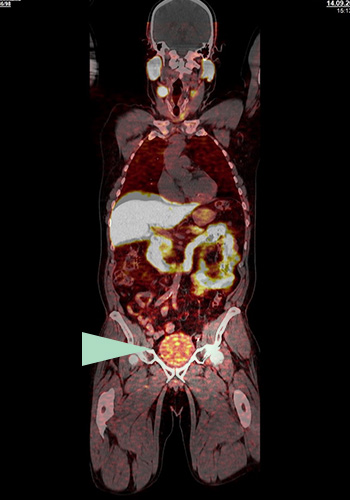

Prostatakrebs

Nachweis eines bisher unerkannten Tumorherdes (s. gelber Pfeil) durch das Fluor-18 PSMA PET-CT links hinter der Harnblase. Die Prostata war mehrere Jahre zuvor operativ entfernt worden. Ein PSA-Anstieg war der Anlass für die Durchführung des PET-CTs.

Bisheriges Präparat mit störender Radioaktivität in der Harnblase (Gallium-68 PSMA)

Mit dem F-18 PSMA PET-CT lassen sich kleine und kleinste Tumorherde und Absiedlungen des Prostatakarzinoms (Metastasen) in Lymphknoten und Organen nachweisen. Auch in der Prostata selbst oder in der Prostataloge wird Tumorgewebe sehr empfindlich detektiert.

Kleinste Tumorherde werden entdeckt (bessere Auflösung)

Tochtergeschwülste (Metastasen) im kleinen Becken und Tumore in der Prostataloge werden zuverlässig gefunden (da keine störende Anreicherung in der Harnblase erfolgt)